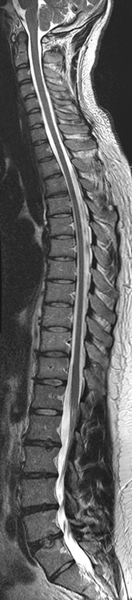

Cervical, thoracic and lumbar spines.

MRI is the preferred method of imaging the spine. Exquisite detail of bones, ligaments, cartilage and the spinal cord with its individual nerve roots are well seen. Pathologies that can be visualized within the spine include fractures, arthritic changes, inflammatory conditions, tumors, MS, traumatic spinal cord injuries, malformations of the blood vessel (AVM or AV Fistula) and disc protrusions.

(left) Cervical spine image. (right) Lumbar spine image showing disc protrusion (arrow).